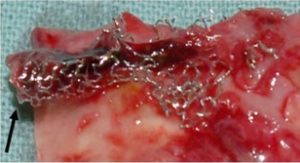

Stents are tiny metal scaffoldings that are used to force open narrow atherosclerotic arteries. (Figure 4) Many improvements in stent technology have been made over the years. As of 2018, we are on our fourth generation of stents. The metal scaffolding mesh has gotten narrower, which promotes the growth of a monolayer of endothelium (endothelialization) or the ability for the arterial tissue to cover up the metal stent. This is necessary for healthy blood flow in the artery and for preventing blood clots forming in the stent, also called in-stent thrombosis.[6](Figure 5) These new stents are also more flexible to bend into tiny arteries, thereby facilitating placement. The most essential function of the drug is to prevent the stent from becoming clogged with the rapid overgrowth of arterial tissue, also known as neointimal hyperplasia; however, as seen in Figure 5, there is a significant trade-off for this protection with the increase of potentially deadly in-stent thrombosis.[6] This is what happened to my younger brother, who died. Clots can also form in the stent due to incomplete apposition (the stent does not fully deploy or open) leaving a gap that may never endothelialize.